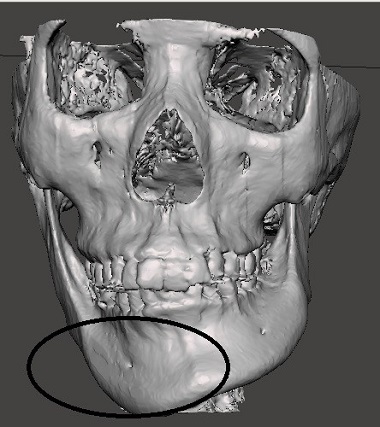

Với kỹ thuật thông thường qua chụp phim X Quang, bác sĩ không thể nhìn rõ những dị tật về xương hay tỷ lệ khuôn mặt không cân đối.

Nhìn trên phim X-quang không phát hiện ra chỗ đầu xương quai hàm bị rỗ.

Với công nghệ 3D, bộ phận kỹ thuật sẽ xử lý file chụp từ máy X quang trên phần mềm 3D, tách các mô, xương, ...

Máy in 3D in ra mẫu xương với tỷ lệ hoàn toàn chính xác như xương thật. Bác sĩ sẽ tiến hành đo đạc, lên phương án phẫu thuật, thực hiện trước trên mẫu xương 3D.

Ảnh 3D sau phẫu thuật

Việc phẫu thuật với mẫu xương 3D không những làm giảm rất nhiều thời gian phẫu thuật thật mà còn đảm bảo độ chính xác gần như tuyệt đối, tránh sai sót trong quá trình phẫu thuật.